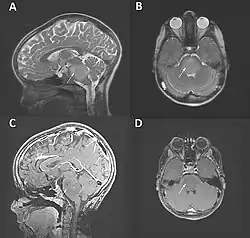

Der Tumor kann mittels Schnittbildgebung, vor allem der Magnetresonanztomographie, dargestellt werden. Der Tumor zeigt keine oder nur eine geringe Aufnahme von Gadolinium-Kontrastmittel.[5][8]